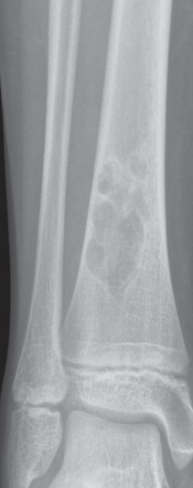

Osteomyelitis

- Destruction of the upper end of the tibia

- Periosteal reaction along the tibia.